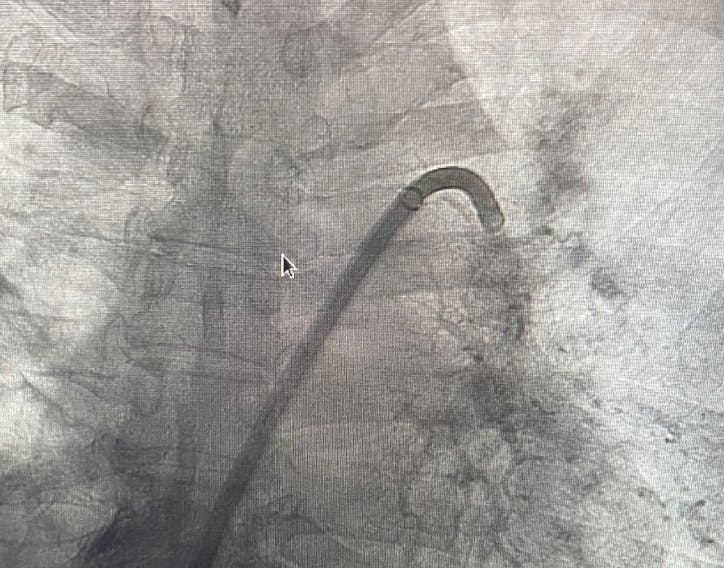

INTERVENTION

Access was obtained in the right groin, and an angiogram was performed to confirm the patency of the inferior vena cava and the iliac veins. Over the wire, a 16-F, 33-cm Gore DrySeal sheath was placed, and a Swan-Ganz PA catheter was advanced to the PA to measure the hemodynamics and measure the cardiac output. After exchanging for the 16-F Lightning Flash aspiration catheter in the right lung, aspiration thrombectomy was initiated (Figure 3).

Figure 3. Intraprocedural angiogram.

Upon confirming vessel patency and thrombus removal with an angiogram (Figure 4, Figure 5, and Figure 6), right heart catheterization from the side port was performed, showing a significant drop in PA pressure from systolic 67 down to 49 mm Hg and excellent hemostasis. By the conclusion of the case, the patient no longer required supplemental oxygen, had no chest pain or shortness of breath, and experienced no significant bleeding. The patient was cleared for discharge the next day.